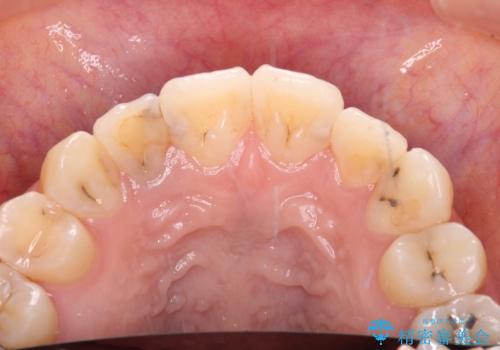

以前治療した前歯をきれいに治したい オールセラミッククラウン

- 根管治療はやり直さずに、ファイバーポストを使用した土台を植立して、オールセラミッククラウンにて補綴することとしました。

神経を取り除いた歯の変色は、クリーニングやホワイトニングでは改善できないため、オールセラミッククラウンなどによる補綴治療が必要となります。